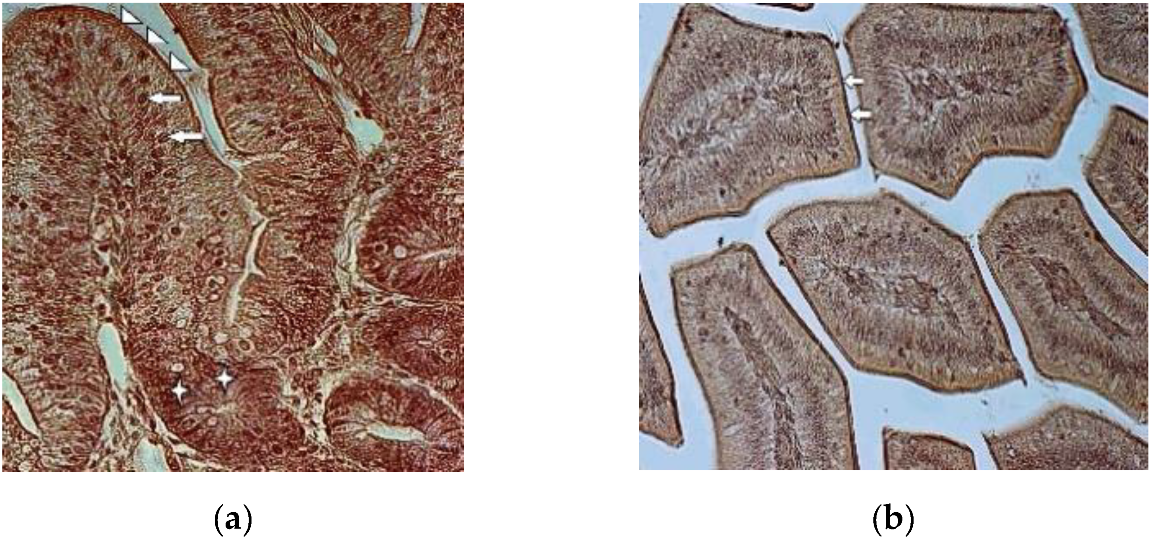

3.2. Immunohistochemistry